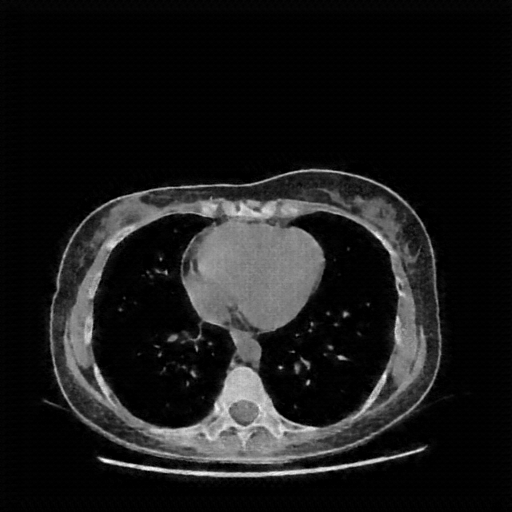

Reconstructed NATIVE CT scan (cycle consistency)

Full window (WL 1023.5, WW 4095 β†’ Low βˆ’1024, High +3071)

Lung window (WL -600, WW 1500 β†’ Low βˆ’1350, High +150)

Mediastinum window (WL 40, WW 400 β†’ Low βˆ’160, High +240)